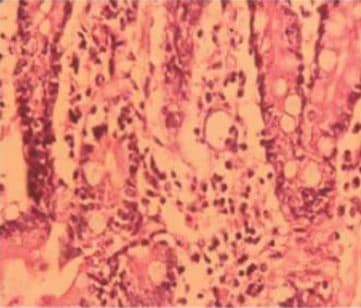

Se realizaron diversos exámenes de laboratorio como parte del protocolo de diarrea crónica dentro los cuales destacan: hemograma que muestra unaanemia (hemoglobina 101 g/L). Grupo sanguíneo: O Rh positivo. Química sanguínea: ionograma, glicemia y calcemia dentro de parámetros normales. Examen general de orina y urocultivo: normal. Test de Felhing negativo. Serología para Rotavirus negativo. Coproparasitológico seriado: negativo. Anticuerpos anti-endomisio elevado: 7 UI/mL (valor de referencia menor a 5.7 UI/mL), Anti-transglutaminasa elevado: 7 UI/mL (valor de referencia menor a 6.0 UI/mL). Biopsia intestinal que informa: relación vellosidad cripta preservada, aumento del número de linfocitos intraepiteliales, MARSH grado I – ll (Figura # 1); con estos resultado se llegó al diagnóstico de enfermedad celiaca.

Figura 1. Biopsia intestinal: linfocitos intraepiteliales aumentados, MARSH I – II